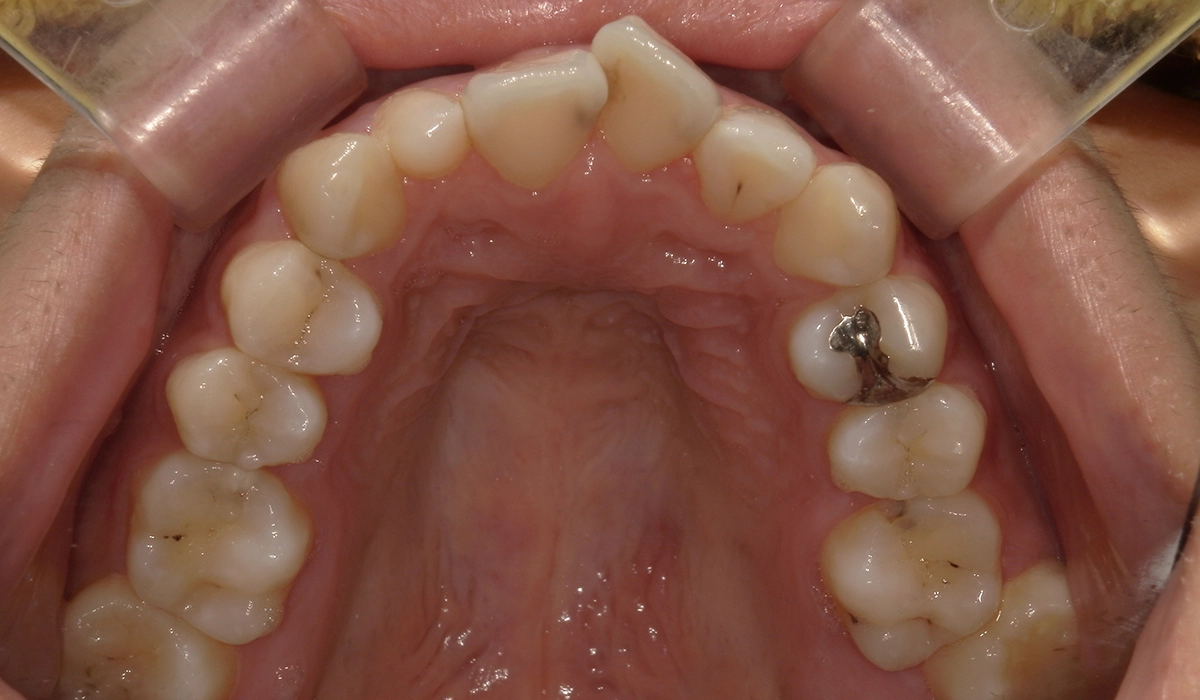

術前:上顎

術後:上顎

今回ご紹介する患者様は、上下の歯並びのガタツキを気にされており、矯正検査後叢生Ⅱ級と診断いたしました。

| 治療内容 | 上下の歯並びのガタツキを気にされており、矯正検査後叢生Ⅱ級と診断いたしました。 |